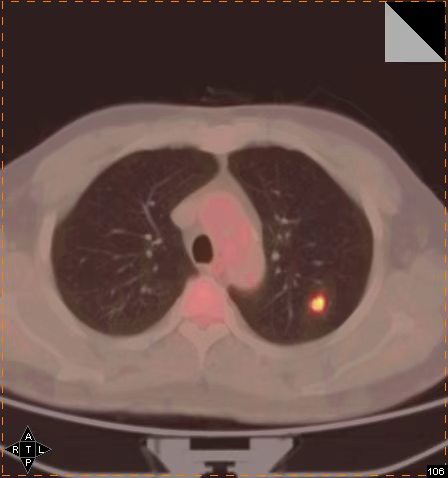

Early cancer screening can involve options like PET-CT.

PET can detect diseases by identifying abnormal functional metabolism in lesions, but it may not provide the precise anatomical location of some abnormalities. In other words, it can indicate the presence of a disease but not always exactly where the lesion is located.

CT can accurately describe the morphology, size, and location of lesions. However, it can only detect the disease once it has progressed to the stage of causing "morphological changes," which often means diagnosis occurs at a later stage. Essentially, it tells you where the lesion is, but sometimes that is already too late.

Thus, the powerful combination of PET and CT led to the development of PET-CT, which integrates the strengths of both "parents" and plays a significant role in the early diagnosis of tumors. Early diagnosis and treatment are key to nipping cancer in the bud. In the era of precision medicine, disease diagnosis and treatment rely not only on histomorphology and pathology but also increasingly on the molecular level. PET-CT excels in this regard. Its precision allows for the detection of minuscule tumors and can probe the molecular level, reflecting the metabolic and functional status of diseased tissues, making it an indispensable tool in the age of precision medicine.